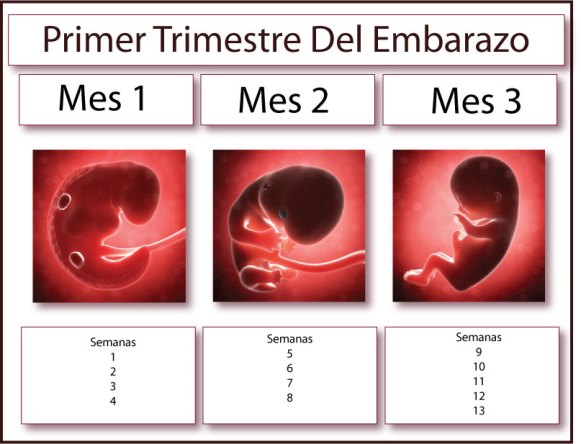

Primer trimestre de embarazo

Las hormonas juegan un papel fundamental. La somnolencia es debida al incremento de los niveles de progesterona que es un sedante natural. Esta hormona trabaja activamente durante las primeras semanas preparando el útero para la implantación del óvulo que ha sido fecundado. Además, es esencial para el mantenimiento del embarazo y para el desarrollo del feto, no obstante, causa algunos efectos secundarios, siendo la sensación de cansancio y el sueño excesivo uno de los principales. Esta hormona que aumenta sus niveles en un 500%, también actúa directamente en el sistema nervioso central, lo que causa problemas para dormir durante el embarazo.

En el primer trimestre, se empieza el desarrollo del feto y es necesario formar la placenta. El organismo empieza a producir más sangre para enviar nutrientes al bebé, haciendo que el corazón y los órganos involucrados trabajen más de lo habitual. El bebé experimenta la etapa inicial de su desarrollo, en la que se forman los órganos principales y ello requiere de energía, haciendo que el cuerpo de la mujer priorice el desarrollo del embarazo, en detrimento de sus actividades diarias.

Como podemos imaginar, en este primer trimestre, el cansancio y el sueño excesivo nada tienen que ver con el peso del feto o el tamaño del vientre.